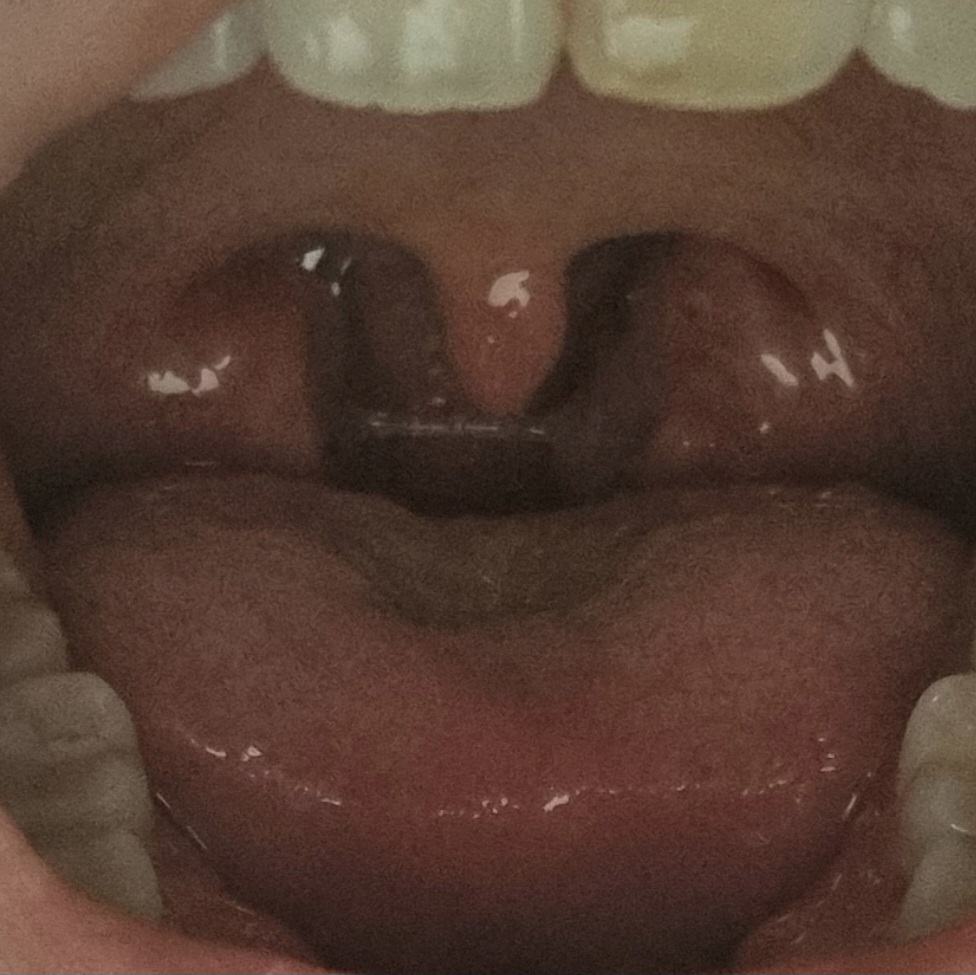

이건 내가 거울보고 찍은거 ㅋㅋㅋㅋㅋㅋㅋㅋㅋ저 양옆에 두 덩어리 들을 제거하는거래